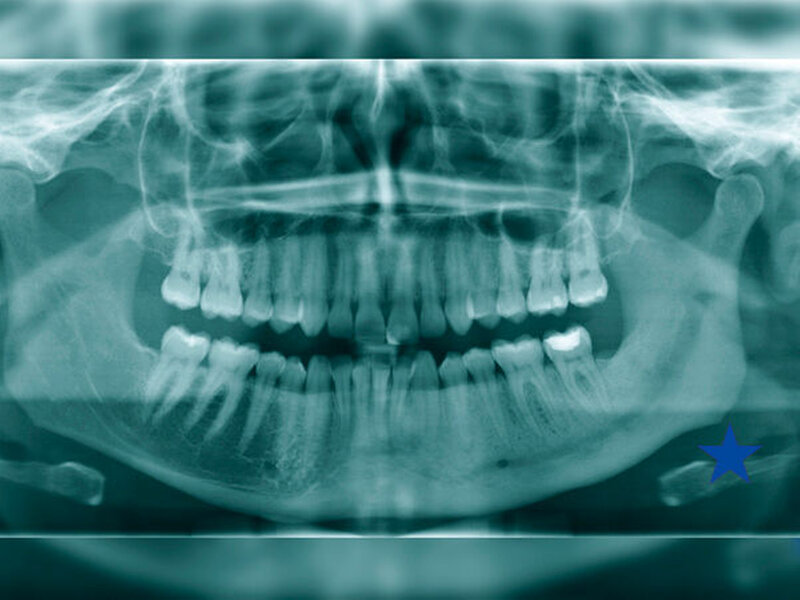

In radiologischen Untersuchungen zeigt sich bei konventionellen Röntgenaufnahmen und in der CT-Bildgebung im betroffenen Kieferareal eine vermehrte Sklerosierung des Knochens ohne Sequesterbildung (Abbildungen 1 bis 3). In der Szintigrafie des Unterkiefers zeigt sich ein chronisch entzündlicher Prozess ohne Anzeichen für eine floride bakterielle Entzündung [van Merkesteyn et al., 1988] (Abbildung 3).